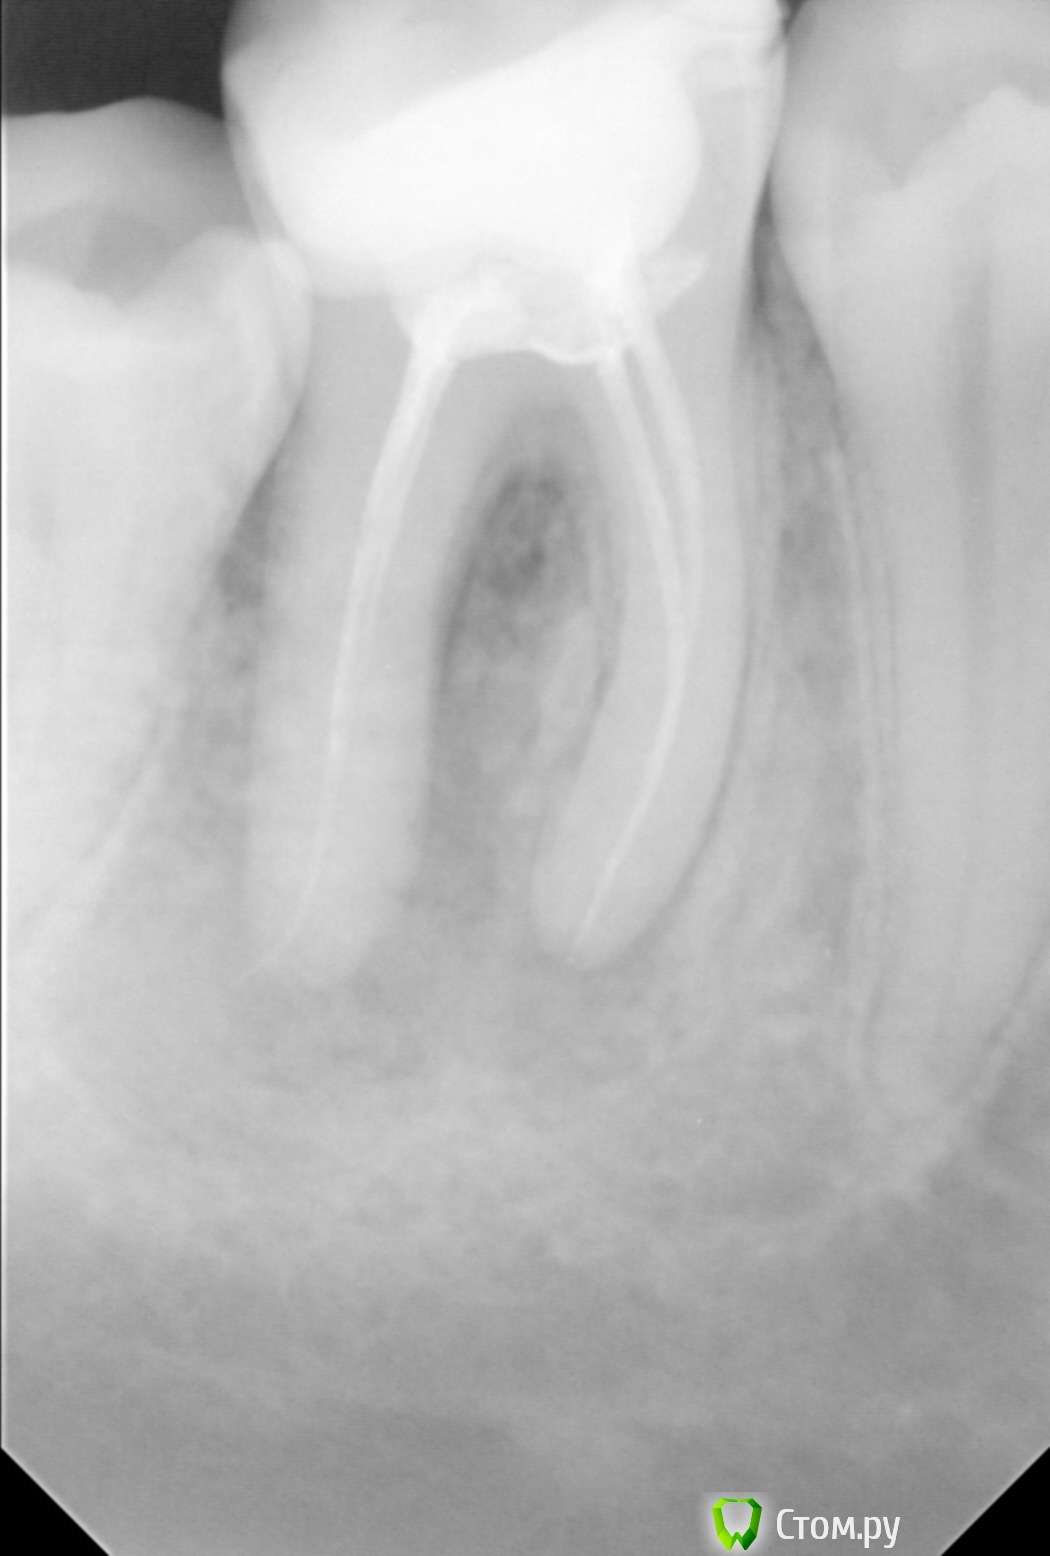

pour toi Опубликовано 2 сентября, 2014 Поделиться Опубликовано 2 сентября, 2014 (изменено) Здравствуйте!Примерно месяц назад начал болеть зуб при жевании, болела десна. Появился свищ, десна и зуб не болят. Стоматолог не смог предложить никакого лечения после рентгеновского снимка. Сказал надо удалять зуб, чего делать, конечно, не хочется. Посмотрите, пожалуйста, снимок и подскажите киста ли это или что-то еще и нужно ли удалять зуб.Заранее спасибо! Изменено 2 сентября, 2014 пользователем pour toi Ссылка на комментарий

shishok Опубликовано 3 сентября, 2014 Поделиться Опубликовано 3 сентября, 2014 Чтобы начать лечение нужно поставить диагноз. А мне его никто не может поставить.В данном случае уточненный диагноз не принципиален.Воспаление на верхушках есть.Методы лечения в принципе одинаковые(открыть каналы,расширить,вымыть,запломбировать). 2 Ссылка на комментарий

Cleric Опубликовано 3 сентября, 2014 Поделиться Опубликовано 3 сентября, 2014 Здравствуйте!Примерно месяц назад начал болеть зуб при жевании, болела десна. Появился свищ, десна и зуб не болят. Стоматолог не смог предложить никакого лечения после рентгеновского снимка. Сказал надо удалять зуб, чего делать, конечно, не хочется. Посмотрите, пожалуйста, снимок и подскажите киста ли это или что-то еще и нужно ли удалять зуб.Заранее спасибо!Здравствуйте!Поищите в своем городе врача-стоматолога эндодонтиста, специалиста по лечению корневых каналов. Если в зубе нет трещины, то вероятность излечения при соблюдении современного протокола лечения - 75%.Рекомендовано проводить лечение с использованием операционного микроскопа. Ссылка на комментарий